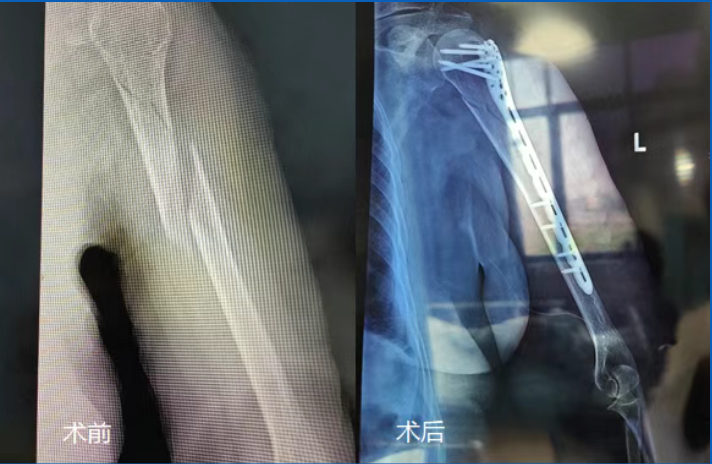

经拍片检查,医生诊断她是左臂上段粉碎性骨折,伴有明显移位。

手术当天早上7点半,李奶奶被推进手术室。麻醉医生先通过超声找到神经,精准打了麻药,完成神经阻滞。李奶奶说:“胳膊有点发热,紧张劲儿也少了”。手术中,医生们手法轻柔,1小时10分钟便完成了骨折复位与固定。等李奶奶在麻醉复苏室醒来,第一句话就是问:“我的胳膊还在吗?”护士赶紧安慰她:“在呢,手术特别成功!”